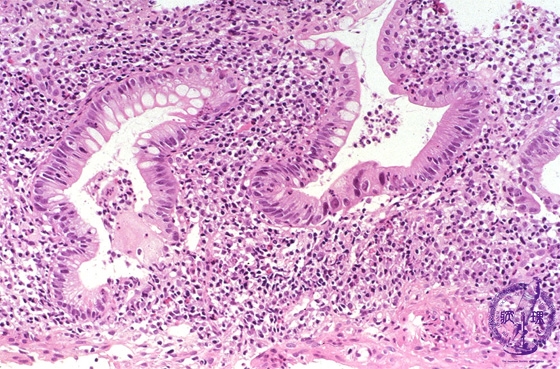

Microscopic view (H&E stain, high power): Acute ulcerative colitis with severe inflammation including crypt abscess formation.

Click the image to see the enlarged image.